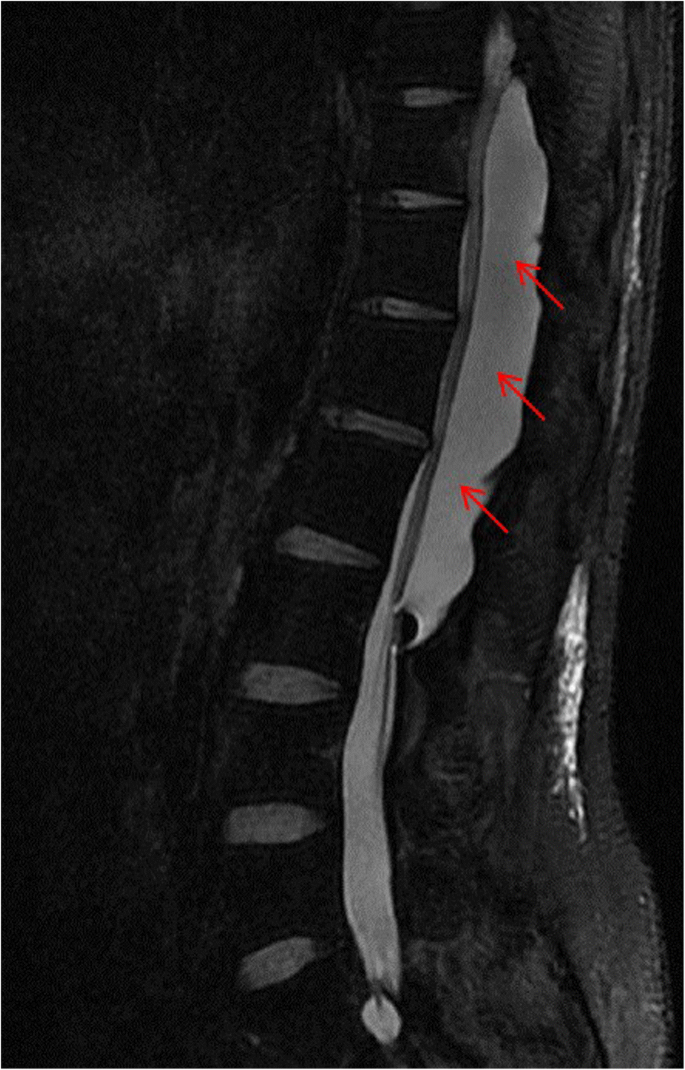

This is a 26-year-old man who experienced right lower limb weakness for 2 years and the weakness exacerbated in last half year. He visited the second affiliate hospital of the Zhejiang University School of Medicine. A physical examination indicated the result of the straight leg raising test was positive and also muscle atrophy. The muscle power of the right lower limb had decreased to grade 3. There was no sensory impairment. Magnetic resonance imaging revealed an intraspinal extradural tumor over T10 to L3 (Fig. 1). It appeared to be a spinal extradural arachnoid cyst (SEAC). To confirm whether the fistula existed between the subarachnoid space and arachnoid cyst, and to localize the position of the fistula, we performed a real-time technique. First, we injected contrast medium into the cyst under fluoroscopy. After 1 h the follow-up computed tomography (CT) was administered, and it revealed there was no contrast-infiltration into the subarachnoid space (Fig. 2). We then extracted about 20 mL of fluid from the cyst. The follow-up magnetic resonance imaging on the same day indicated the cyst did not become smaller (Fig. 3). A “one-way valve” fistula was suspected such that cerebral spinal fluid could pass into the cystic space from the subarachnoid space but could not flow in the opposite manner. Therefore we designed a procedure to localize the fistula. We penetrated two needles into the cyst and subarachnoid space separately in the L3/L4 level under digital subtraction angiography (Fig. 4). Pending the fluid drained through those two needles, we injected 10 mL of contrast medium slowly into the subarachnoid space and a little contrast medium infiltrated into the cystic space horizontally at the T12/L1 level. We then administered high resolution computed tomography (HRCT) immediately to confirm the position in the axial plane. The HRCT revealed a funnel-shaped enhancement between the lower edges of the T12 body and the left nerve root, and this is the accurate position of the fistula (Fig. 5).